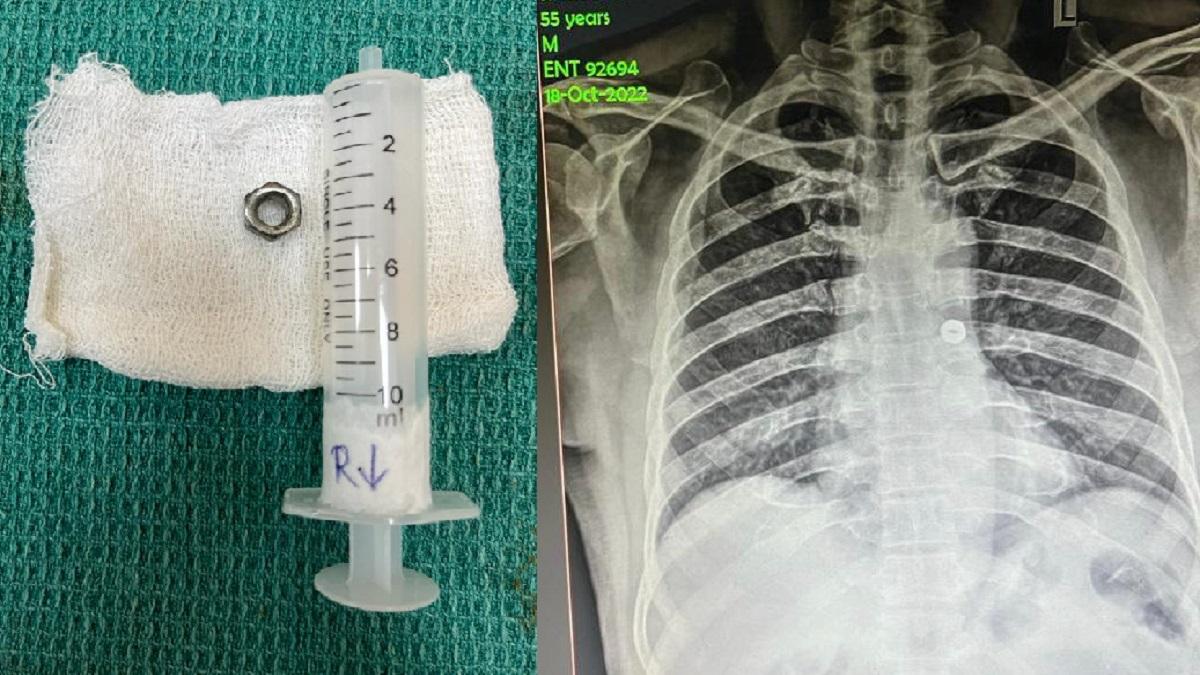

तमिलनाडु में कोयंबटूर के सरकारी अस्पताल में डॉक्टरों ने गलती से लोहे का नट निगल लेने के चलते मुसीबत में पड़े 55 साल के शख्स की जान बचाई है. शमशुद्दीन नाम का शख्स इलेक्ट्रिशियन का काम करता था. 18 अक्टूबर को काम करते हुए उसने गलती से एक लोहे का नट निगल लिया.

शमशुद्दीन ने नट को खांसकर बाहर निकालने की कोशिश की, लेकिन उसका दम घुटने लगा. इसके बाद उसे आनन फानन में सरकारी अस्पताल में ले जाया गया. उसे अस्पताल के ईएनटी विभाग में ले जाकर तुरंत उसका एक्स-रे किया गया.

एक्स-रे में डॉक्टरों ने देखा कि नट उसकी सांस नली में अटका  हुआ था और उसके बाएं फेफड़े की ओर जा रहा था. इसके बाद कान, नाक और गले विभाग के प्रमुख डॉ. सरवनन, डॉ. अलीसुल्तान और एनेस्थिसियोलॉजी विभाग के डॉ. मनीमोझी,सेलवन और मदनगोपालन की टीम ने एंडोट्रैचियल इंस्ट्रूमेंट का उपयोग करके शमशुद्दीन का ऑपरेशन किया और नट को सफलतापूर्वक निकाल दिया. तुरंत इलाज के चलते ही शमशुद्दीन की जान बचाई जा सकी.